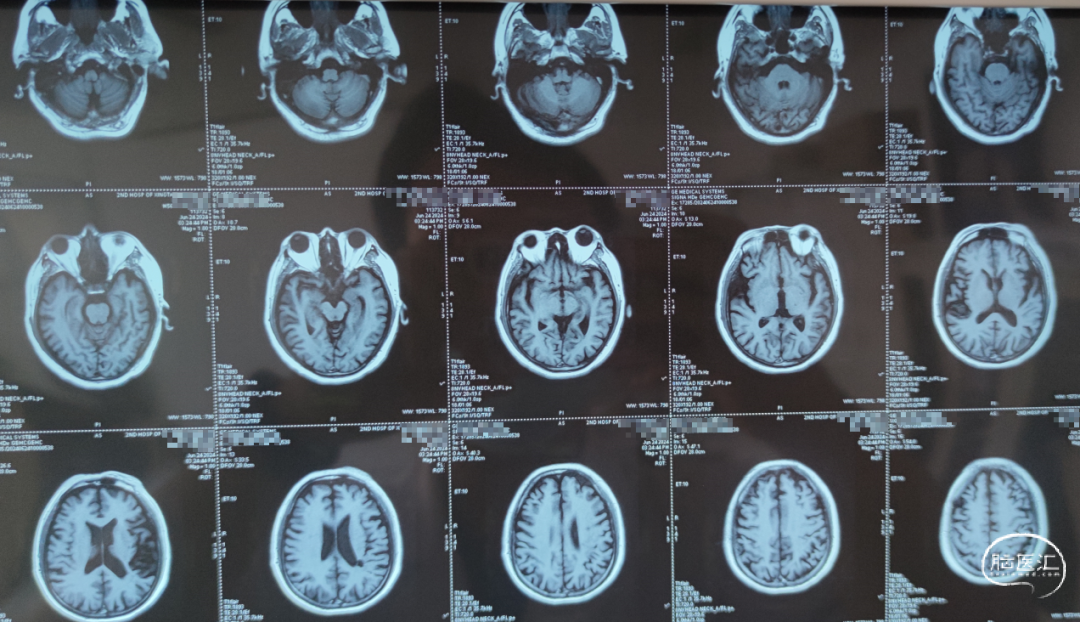

头颅MRI:未见新鲜脑梗死

➢术后头颅CT